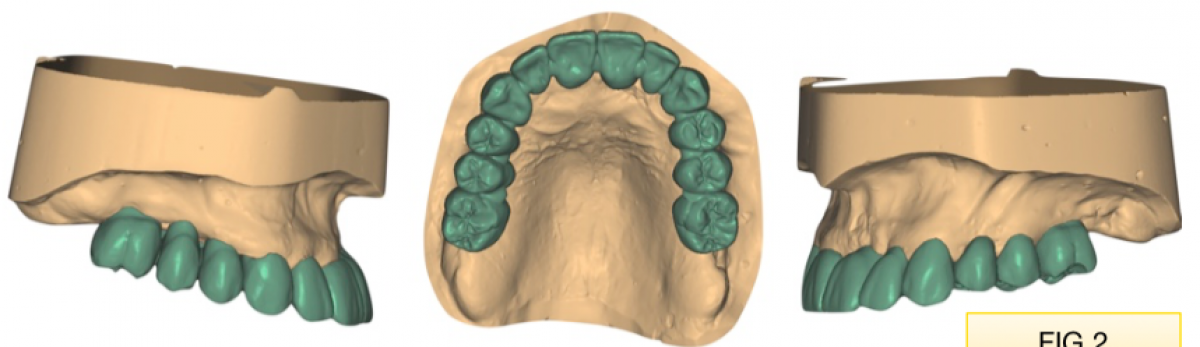

The therapeutic project start with taking impressions of the area that will undergo the surgery, the antagonist area and the bite-block by means of an intraoral scanner.

Facial scans, useful both as STL files and pre-surgical image documentation, are also taken. The following phase includes the patient undergoing a CBCT scan with stent, being it an extra oral geometry needed in order to re-align the CBCT files!"DICOM with the STL ones from the intra oral and facial scansion. In the next step condylar movements are registered with Prosystom software.

The latter collects condylar movement in left and right laterality, opening and closing, singularly revealed and in complete masticatory pattern. Data are afterwards exported in a reading format by exocad software.

The files from the intraoral scansion, facial scansion, CBCT and axiography are paired in the soft- ware in order to realise a diagnostic waxing with individual values. FIG 2

The diagnostic waxing, paired with the files from the CBCT, allows us to accurately choose the right position for implant placement by analysing quality and quantity of bone in relation to the future position of teeth.

This approach is defined as prosthetically guided surgery and allows the placement of a provi- sional that is able to follow the habitual masticatory pattern of the patient, before the surgical pro- cedure.